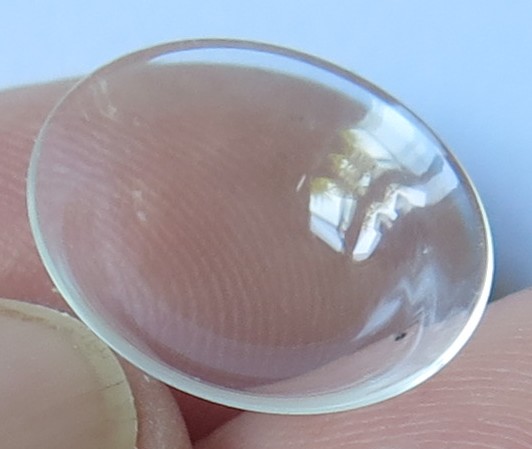

Een kleine greep uit ons aanbod